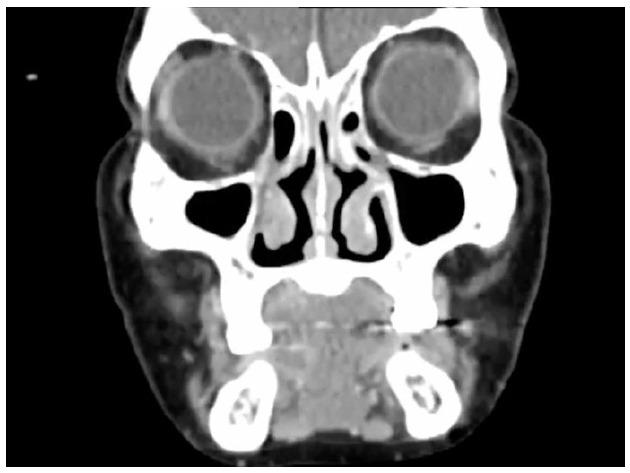

Primary lymphoma originating from the lacrimal drainage system is a rare disease. Such lymphomas are mostly B-cell in origin and present nonspecific symptoms. The treatment of malignant lymphoma of the lacrimal drainage system is slightly different. We present the case of a 71-year-old woman with a painless mass below the medial canthus. Computed tomography (CT) scan of the orbit revealed a mass invading the right lacrimal sac. An incision biopsy was obtained, and the pathologic findings suggested a diagnosis of primary diffuse large B-cell lymphoma of the lacrimal sac. The patient was treated with chemotherapy and intrathecal methotrexate. After completing eight cycles of chemotherapy, the patient was followed up by a CT scan, which revealed nearly total resolution of an ill-defined enhancing mass. At the time of this case report writing, the patient is in complete remission at six months with no other complications.